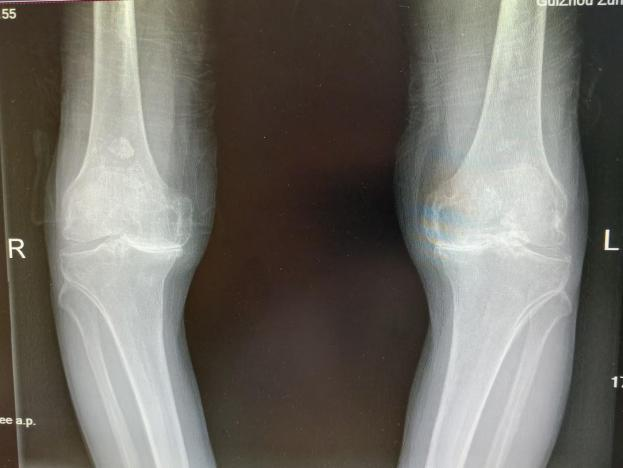

为提升区域内基层医疗机构糖尿病足诊疗服务能力、促进青年医师对糖尿病足的规范化诊治水平,遵义市第二城市医疗集团总院(贵州航天医院)圆满举办贵州省继续医学教育项目——胫骨横向骨搬移技术治疗糖尿病足专题研讨班。 贵州航天医院党委委员、副院长彭亮出席会议并致辞,遵义市第二城市医疗集团各成员单位,以及红花岗区、汇川区、绥阳县、桐梓县等多个区县的基层医疗机构骨干医师参加会议。 研讨班 本次研讨班以胫骨横向骨搬移技术在糖尿病足治疗中的应用为核心主题,围绕糖尿病药物治疗与生活方式管理策略、围手术期血糖精准调控要点、胫骨横向骨搬移技术典型病例深度解析、糖尿病足的临床分型与个体化治疗方案制定等临床实践中的热点与难点展开深入探讨,通过专题授课、案例研讨、互动交流等多元化形式,为参会者搭建了理论与实践结合的学习平台。 此次研讨班不仅为区域内基层医院搭建了学术交流与经验共享的平台,更对推动糖尿病足预防、诊断与治疗的规范化、系统化发展起到了积极作用,有效助力青年医师更新专业知识体系、提升临床技能,为进一步保障区域内糖尿病足患者的健康奠定了坚实基础。 贵州航天医院骨科专家简介 陈明勇 骨一科主任,副主任医师 临床擅长:从事创伤骨科工作约20年,对骨缺损、骨不连、骨肿瘤、肢体畸形等的肢体矫形重建及功能重建,慢性化脓性骨髓炎的根治治疗、糖尿病足的保肢治疗、快速康复理念(ERAS)下的老年骨折的诊治,四肢复杂骨折的诊治,四肢骨折等微创手术治疗具有丰富的临床经验。 2004年毕业于遵义医学院临床专业,曾在中国人民解放军总医院、广西医科大学第一附属医院、上海第六人民医院骨科进修。中国中西医结合学会骨伤科专业委员会横向骨搬移治疗糖尿病足及微血管网再生学组首届委员,遵义市医学会创伤分会常务委员。 瞿 晖 骨科党支部书记,骨二科主任,副主任医师 临床擅长:对骨科的常见病、关节外科、脊柱外科及运动医学疾病的诊治具有丰富的临床经验,熟练掌握骨科手术操作技术。 毕业于遵义医学院临床医学系,2005年前往广州中山大学第一附院骨显微医学部进修学习,2011年前往成都华西医院进修学习,并多次在省内外学习骨科相关知识,是中华医学会骨科分会会员。 赵小锋 中共党员,骨二科副主任,副主任医师 临床擅长:从事骨科临床工作11年,对骨科常见病、多发病诊疗有较为丰富的临床经验,擅长脊柱相关疾病诊断及治疗,尤其是颈、腰、腿疼痛疾病诊断及治疗,擅长胸腰椎骨折微创经皮穿刺内固定术、经皮穿刺椎体成形术、经皮穿刺脊柱内镜下腰椎间盘摘除术、单纯开创腰椎间盘摘除术、腰椎滑脱复位椎间植骨椎融合内固定术、腰椎管狭窄减压融合内固定术及人工髋、膝关节置换术等。 2012年毕业于遵义医学院外科学专业硕士研究生,2019年参加“遵义市115医学人才精英计划”于上海交通大学第一附属医院培训学习,2023年于北京大学第三人民医院脊柱外科进修学习,曾获得遵义市优秀医师荣誉称号。 遵义市手外科第一届委员,遵义市医学会创伤分会第一届委员,遵义市医学会创伤分会第二届委员,贵州省康复医学会第三届脊柱脊髓专业会委员,遵义市医学会烧伤与整形外科学分会委员,发表论文5篇,其中国家级核心期刊1篇,SCI论文1篇,主持市级课题1项并结题,参与市级课题2项。 赵兴东 骨科主任医师 临床擅长:擅长骨科的常见病及各种创伤、四肢骨折创伤修复、骨感染、手足疾病的诊治和手足体表畸形的矫形整复,熟练掌握骨科四肢骨病及创伤的手术操作技术,尤其在四肢关节复杂性损伤、手足外伤、组织缺损创面、难治创面的皮瓣修复方面及平足、高弓足矫形方面及四肢慢性疼痛诊治、康复方面具有丰富的临床经验。 硕士研究生,毕业于遵义医学院临床外科系,2015年前往山东省立医院手足外科进修学习;遵义市医学分会创伤分会第一、二届委员,遵义市手外科医学会第二委届员会常务委员;在省级及省级以上期刊发表文章9篇,参编著作2部,参与主持并完成市级课题1项,参与市级课题2项、省级课题1项。 张艳金 中共党员,骨科副主任医师 临床擅长:从事骨外科工作16年,对复合伤、多发伤的救治、四肢骨干骨折、关节周围骨折、骨肿瘤、骨髓炎等诊治具有丰富的临床经验。 中共党员,硕士研究生,2006年本科毕业于山西医科大学第二临床医学院,2011年研究生毕业于北京军区总医院;在“老年COPD患者合并髋部骨折的诊治”国际合作课题组研究两年,在老年髋部骨折的诊治方面具有丰富的经验,并发表论文6篇;主持遵义市级课题1项,承担遵义医科大学的临床教学工作,获得遵义医科大学优秀带教老师荣誉。编撰有《骨科疾病诊疗精粹》一书,开展2项新技术,编撰地方规范《务川自治县创伤骨科常见疾病诊疗规范》一书。 张俊凯 骨科副主任医师 临床擅长:从事骨科临床工作28年,对创伤骨折、骨感染、骨缺损、骨不连等外科诊治,四肢骨折的微创手术治疗,四肢复杂骨折(如关节内粉碎性骨折、多发骨折等)的损伤控制及手术治疗等具有丰富的临床经验。 1995年毕业于遵义医学院临床专业,2009年前往复旦大学附属医院骨科进修1年。 卢懿明 中共党员,骨科副主任医师 临床擅长:从事骨科工作18年,对创伤骨折、四肢骨折的微创手术治疗、四肢复杂骨折(如关节内粉碎性骨折、多发骨折等)的损伤控制及手术治疗,尤其是髋部骨折的PFNA等微创技术,踝关节骨折、膝关节周围骨折的Mipo微创技术等具有丰富的临床经验,开展了4项新技术,发明6项新型专利技术。 2005年毕业于遵义医学院临床专业,2017年,前往南方医科大学第三附属医院骨科进修半年,回院后运用Mipo技术对骨干骨折及干骺端骨折的治疗技术,同时积极开展骨盆骨折、髋臼骨折腹直肌外侧切口的应用;发表了多篇专业论文,经常参与省内外学术交流会授课,获得医院荣誉称号多个。 邬夏荣 骨科副主任医师 临床擅长:从事骨科工作16年,对四肢复杂骨折、骨肿瘤的诊治,尤其是足踝创伤、慢性踝关节损伤、平足症等诊疗具有丰富的临床经验。 2006年毕业于遵义医科大学临床医学专业,曾在陆军军医大学西南医院进修学习,发表多篇骨科学术论文。 余德怀 中共党员,骨科副主任医师 临床擅长:从事骨科工作10余年,对运动医学、骨关节、脊柱外科常见病、多发病的诊治具有丰富的临床经验。 硕士研究生,2011年毕业于遵义医学院临床医学专业,曾前往遵义医科大学附属医院运动医学专业进修学习;是贵州省医学会运动医学分会青年委员,西部关节镜联盟委员;发表多篇骨科学术论文。 冯 乾 骨科副主任医师 临床擅长:从事骨科工作近20年,熟练掌握骨科多发病及常见病的诊治,尤其对脊柱退变性疾病的诊断及治疗具有丰富的临床经验,主要研究脊柱微创相关治疗方式,能熟练开展椎间孔镜及UBE。 曾前往北京大学第三医院进修学习疼痛及椎间孔镜、首都医科大学友谊医院专业进修脊柱内镜;是贵州省康复医学会第三届脊柱脊髓专业委员会委员;发明专利3项、发表脊柱外科专业论文多篇。 贵州航天医院骨科简介 基本情况 贵州航天医院(原3417医院)骨科组建于1968年,前身是以创伤和断肢(断指)再植闻名于世的上海市第六人民医院骨科,中国断肢(断指)再植的奠基者、中科院院士陈仲伟等专家莅临科室指导医疗和教学,并在70年代开展了贵州省首例断肢(断指)再植手术。组建50余年来,诊治患者已逾百万,挽救了无数的伤病员,成为了保障遵义地区人民群众健康的重要支撑。 经过几代人的不懈努力,今天的骨科,已由创伤骨科发展至骨病、骨肿瘤、骨结核等领域,现有脊柱外科、关节外科、四肢创伤、手足外科四个亚专科,成为了集医疗、教学、科研于一体的综合学科,是贵州省临床重点专科、遵义市临床重点专科、遵义市骨科临床医学中心、遵义市基层骨科专科联盟理事长单位。 科室目前开放床位110张,共有医护人员50余人,副高级以上专家18人,硕士研究生15人。拥有一流骨科医疗设备多台,每年不定期选派优秀技术骨干到全国各大知名医学院校进修、学习、参观、交流,并邀请国内、国外知名专家教授来院进行交流、指导,通过不断引进国内外先进的诊疗技术,科室医疗技术水平稳步提升,为广大人民群众提供了优质的医疗服务。 专科特色 骨一科 (一)骨缺损、骨不连的肢体与功能重建 胫骨横向骨搬移技术治疗糖尿病足: (二)慢性骨髓炎的根治治疗 (三)肢体缺血性疾病如糖尿病足、脉管炎的保肢治疗 (四)皮瓣修复 (五)复杂创伤的治疗 (六)老年髋部骨折及小儿骨折快速手术 老年髋部骨折: 骨二科 (一)胸腰椎骨折微创经皮椎弓根螺钉固定术 (二)老年性骨质疏松性患者腰椎滑脱脊柱内固定术(骨水泥螺钉) (三)V形双通道脊柱内镜技术(VBE)腰椎融合术治疗腰椎退行性疾病 (四)老年性骨质疏松性骨折(PVP/PKP)术 (五)人工髋关节置换术 (六)双侧股骨头坏死人工全髋关节置换 (七)右侧全髋置换术后假体周围骨折翻修 (八)人工膝关节置换术 (九)人工膝关节假体松动翻修 (十)关节镜技术 传统手术切口 关节镜技术切口 诊疗范围 骨一科 1.四肢创伤、矫形。 2.手、足踝外科。 骨二科 End